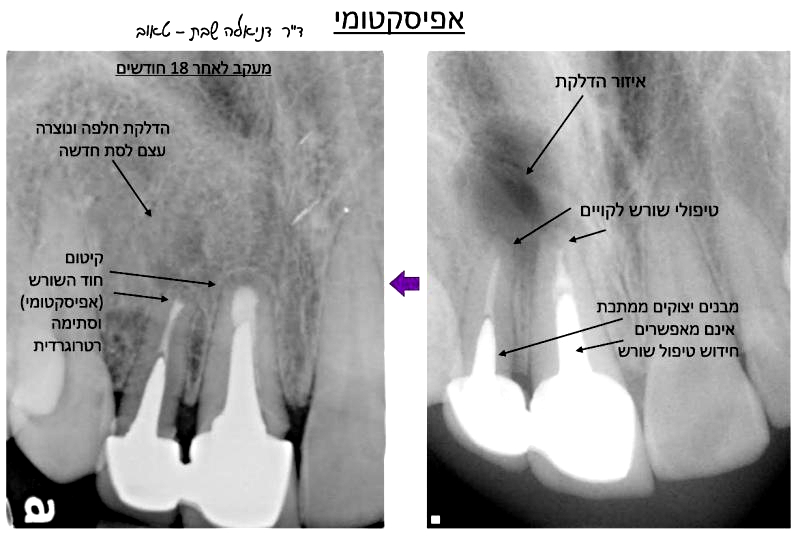

בשתי הדוגמאות הנ"ל גם אם אין כאבים והשן קיבלה כתר איכותי, הרי שמראש טיפול השורש למעשה נכשל, ולאחר זמן מה יצוצו שוב הכאבים והדלקת. ברבות הזמן חיידקים אלו שוב יתרבו וישגשגו, והזיהום שייצרו יתפשט אל קצה השורש ומעבר אליו – לעצם ולרקמות שסביב השורש. בצילום הרנטגן נראה איזור כהה, מוצלל, סביב שורש השן, שמעיד על הדלקת. במילים אחרות – כישלון של טיפול השורש.

אם בבדיקה רנטגנית מתגלה טיפול שורש לקוי ו/או איזור דלקת סביב שורשי השיניים, על הרופא להסביר את המצב למטופל ולהתריע בפניו על הסכנות הטמונות לשן זו. רגע לפני שעוקרים שן רקובה שהתפתחה בה דלקת בעצב, או שן שסביב טיפול שורש ישן התפתחה דלקת, כדאי לבדוק את האפשרות של הצלת השן, ע"י טיפול שורש או חידוש טיפול שורש. לעיתים אין ברירה ויש צורך בטיפול כירורגי אנדודונטי שנקרא אפיסקטומי, ובו מוסר בצורה כירורגית קצה השורש הדלקתי

דוגמא לאפיסקטומי

(טיפול אנדודונטי כירורגי לקיטום חוד שורש דלקתי) ולסתימה רטרוגרדית